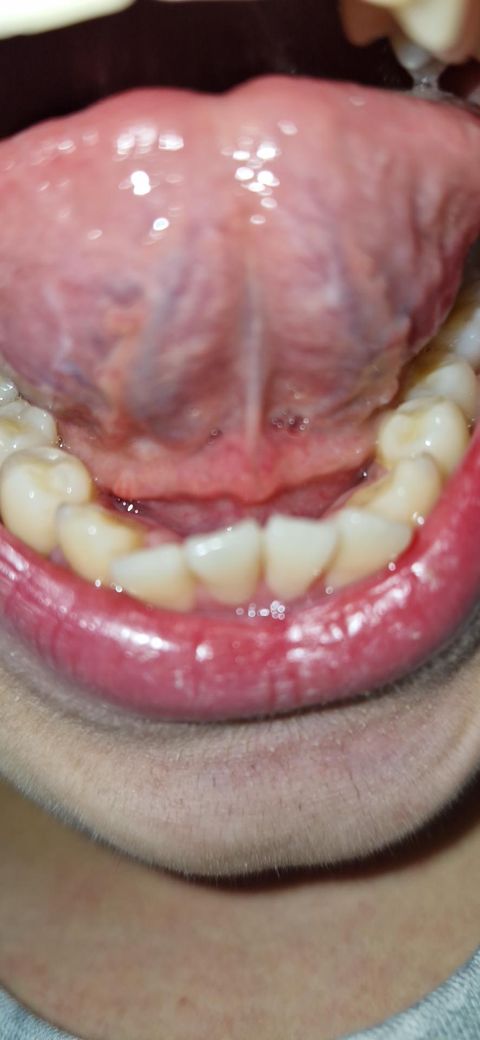

혀 밑에 원래있는건가요, 부은건가요?

혀 밑에 이상한 살점? 같은게 있어요. 이쪽이 아프거나 하지는 않는데 뭔가 부어있는 것 같아요. 원래부터 있던 건가요? 정상적인 상태라 그냥 놔둬도 되는건가요?

원래 잇는 구조물이고 혀가 움직일때 근육처럼 수축되서 보이는거니 크게 걱정하지 않으셔도 됩니다.

해당 부위는 sublingual fold 내지는 sublingual gland인데요 정상보다 살짝 부어있긴 하네요 구강내과가서 진료 받아보시기 바랍니다